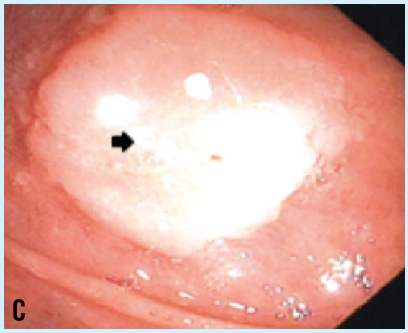

Christine R. Totri, MD, MAS; Ncoza Dlova, MBChB; Anisa Mosam, MBChB, PhD; Nokubonga Khoza, MBChB

A 6-year-old girl presented with a 1-year history of verrucous papules on the lips and oral mucosa extending to the surrounding skin, consistent with HPV infection.